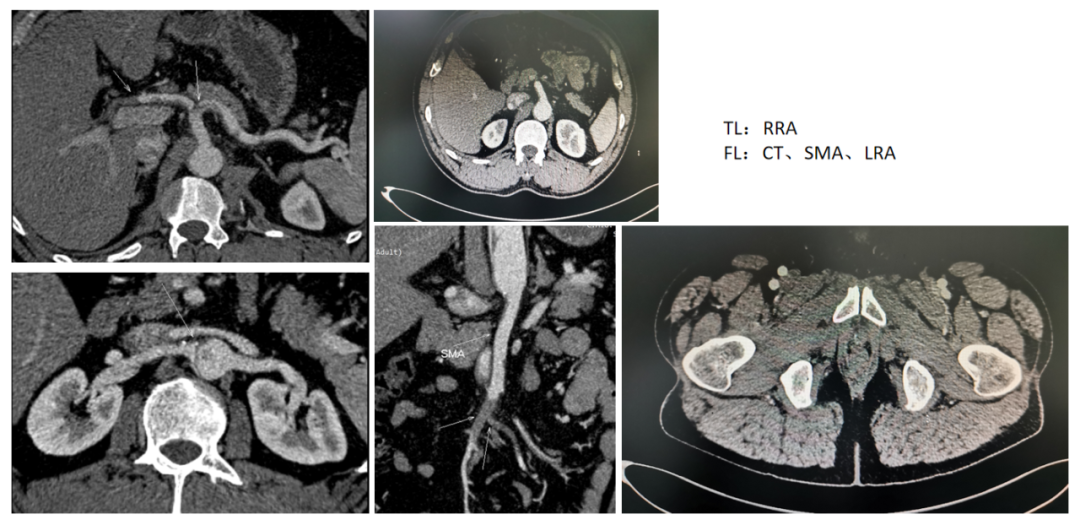

34岁男性,SMI灌注不良,TEVAR后SMA重建

② 脏器灌注不良(SMI)

急性复杂型B型AD(急性期、超急性期):观察期内降压对症治疗,症状无缓解则急诊治疗,首选TEVAR。

TEVAR的目标:

1)封堵主动脉原发破口

2)扩大真强腔,改善脏器分支动脉供血

SMA缺血无改善:SMA重建、支架置入。肠坏死时考虑开腹或腔镜手术。